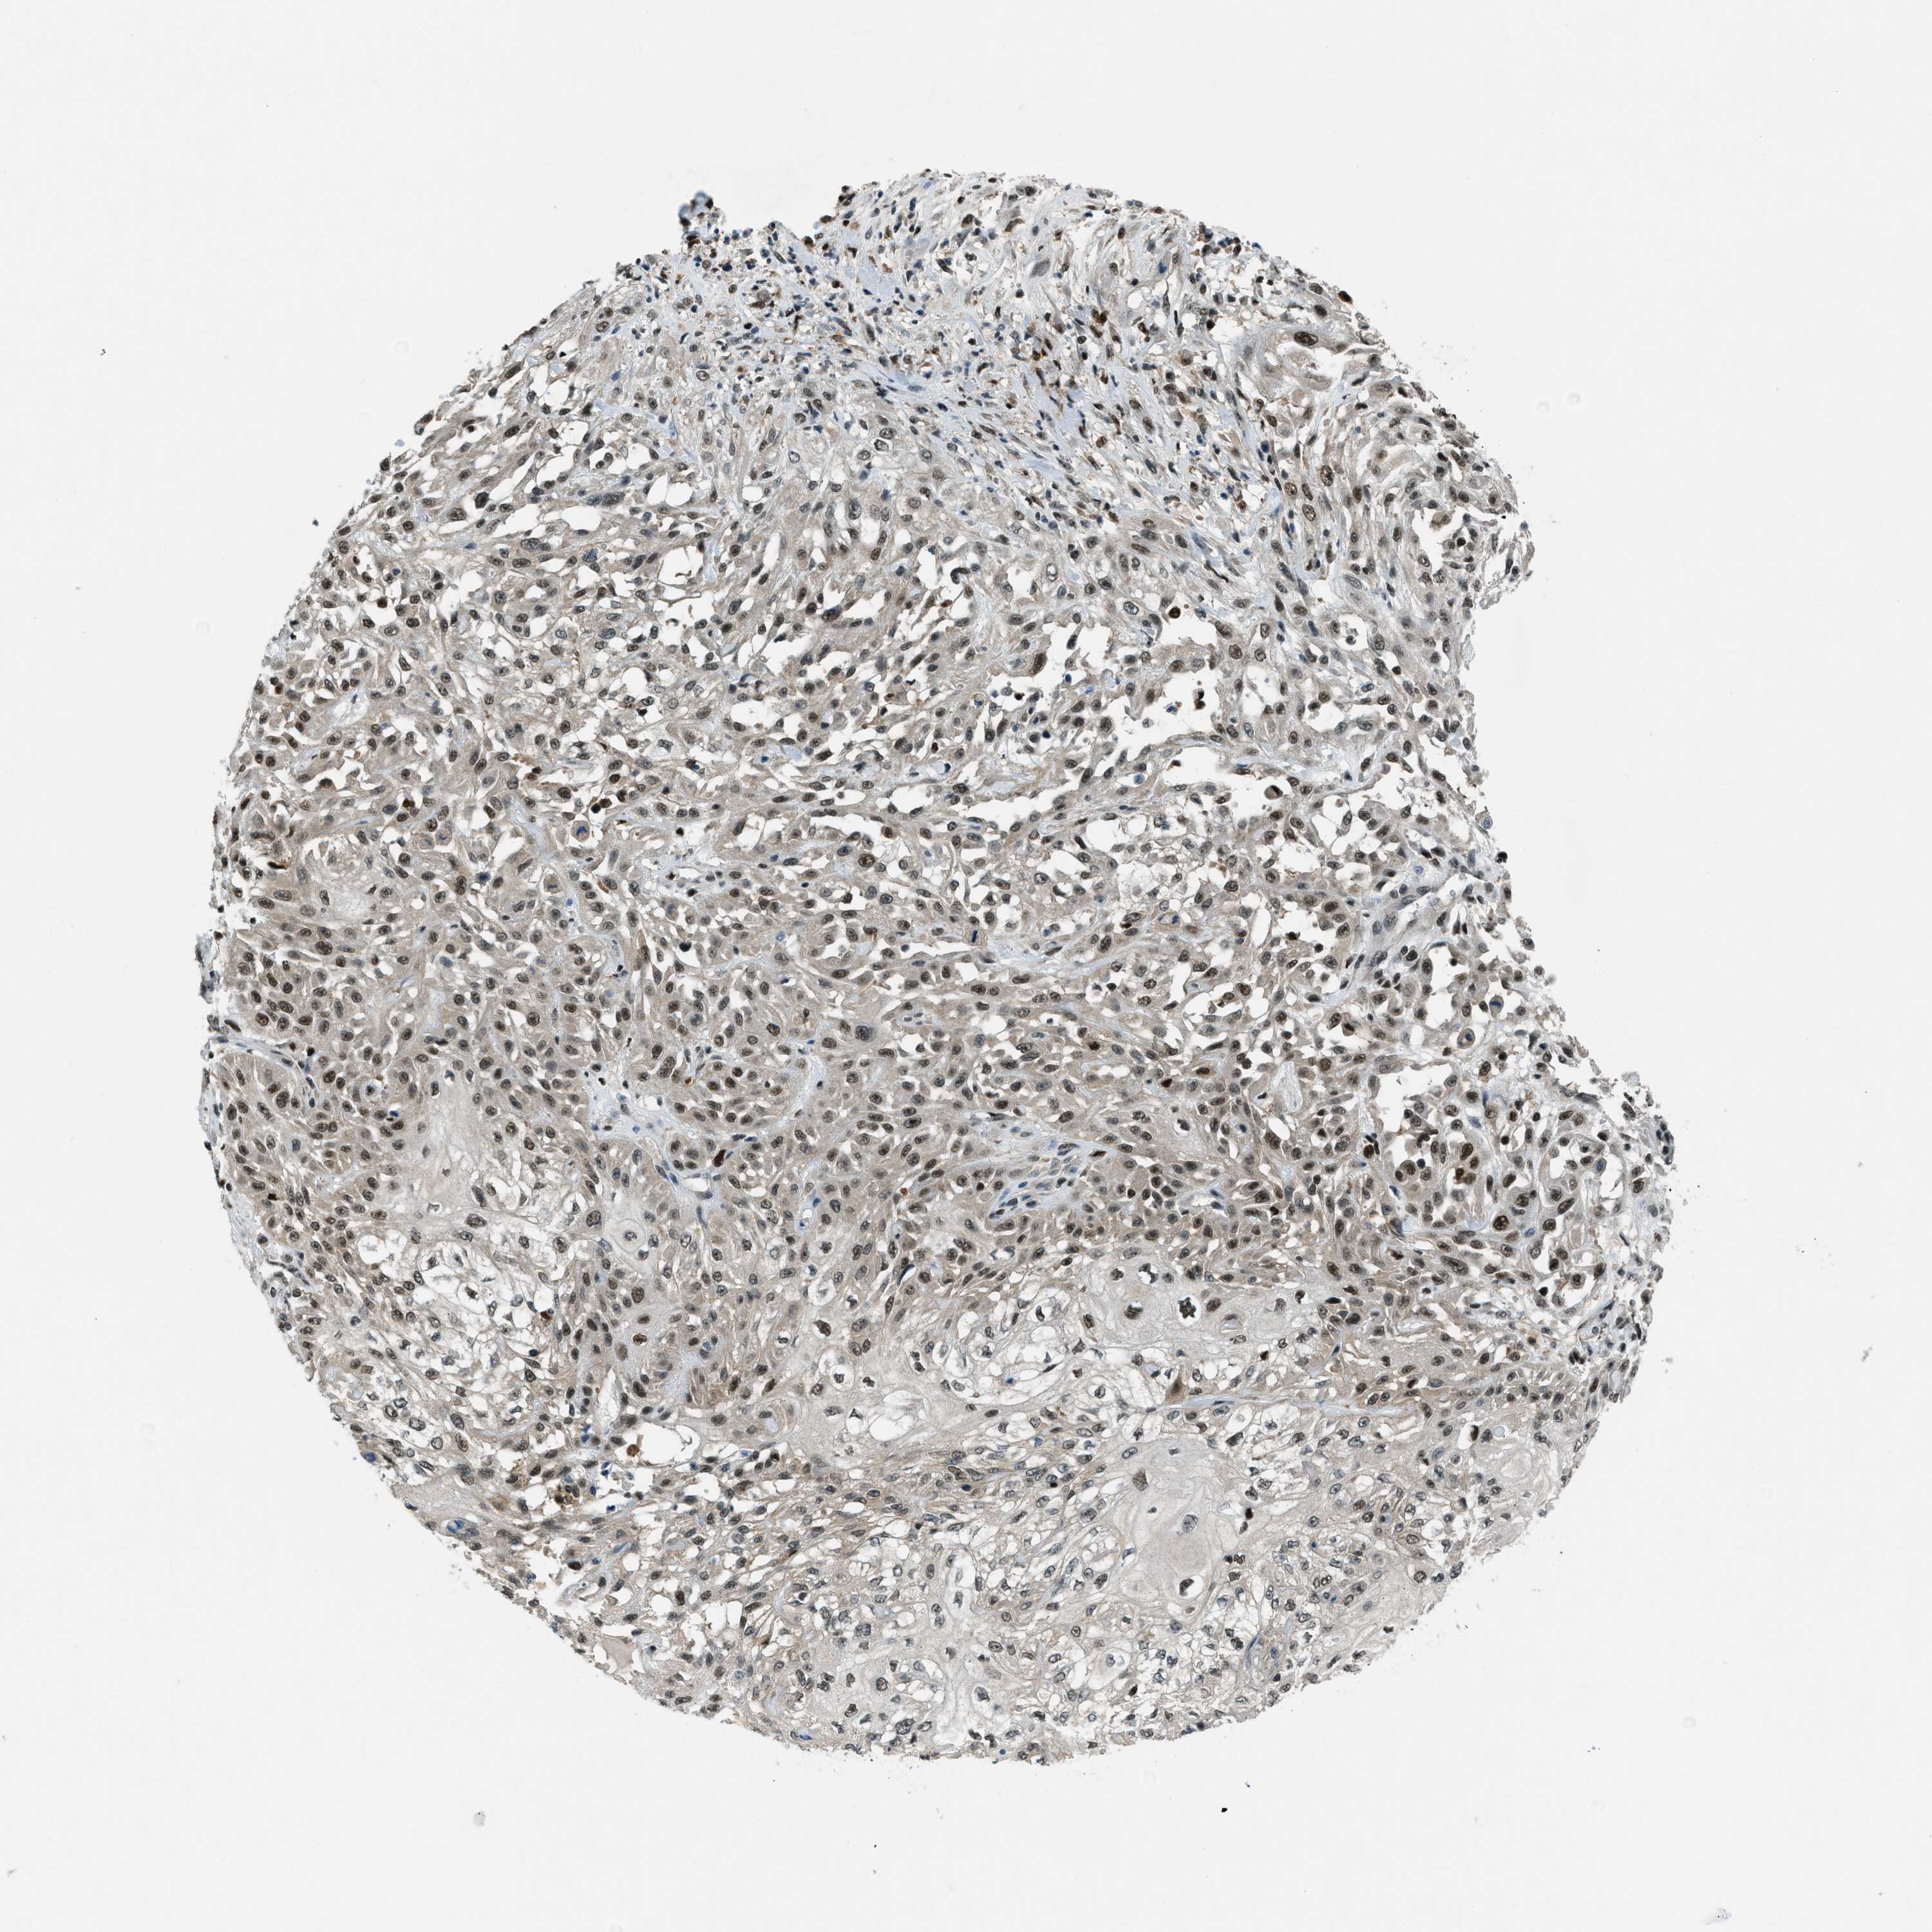

SKIN CANCER - Protein expressioni

A mouse-over function shows sample information and annotation data. Click on an image to view it in a full screen mode. Samples can be filtered based on level of antibody staining by selecting one or several of the following categories: high, medium, low and not detected. The assay and annotation is described here.

Each image is clickable and will lead to virtual microscopy that enables deeper exploration of all samples and also displays staining intensity scores, fraction scores and subcellular localization as well as patient and tissue information for each sample.

Antibody HPA017899

Staining

High

Intensity

Strong

Quantity

>75%

Location

Nuclear

Squamous cell carcinoma, NOS